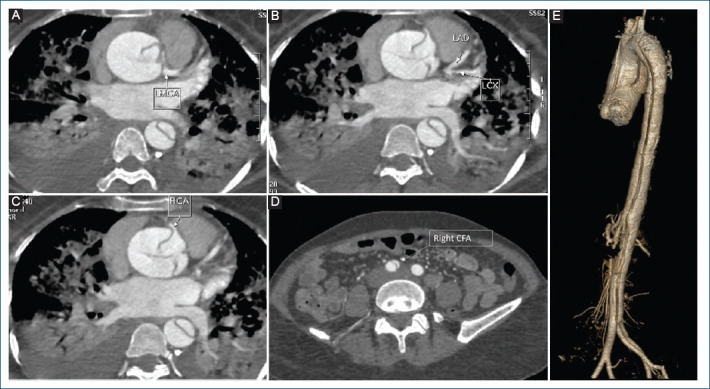

Look before you leap! - A case report of left main dissection causing myocardial infarction.